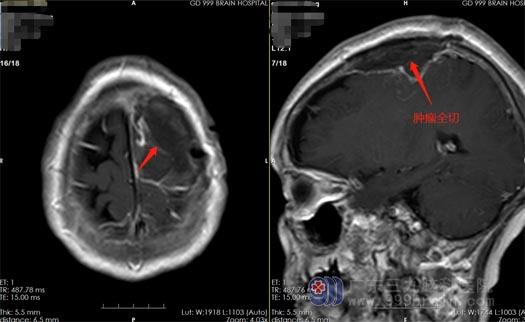

当地医院的头颅CT检查结果提示“左侧顶叶占位性病变,性质待查”,医生建议去上级医院进一步诊治。在广东三九脑科医院神经外五科,曹阿姨做了更详细的检查,头颅MR提示“左侧顶部颅骨内板下占位性病变,大小约为28mmx27mmx26mm,考虑脑膜瘤的可能。”神经外五科的治疗团队一致认为手术是最佳的治疗方案。10月29日,曹阿姨进行了“左侧顶部脑膜瘤切除术”,手术很成功,在显微镜下全切了肿瘤。

▲术后